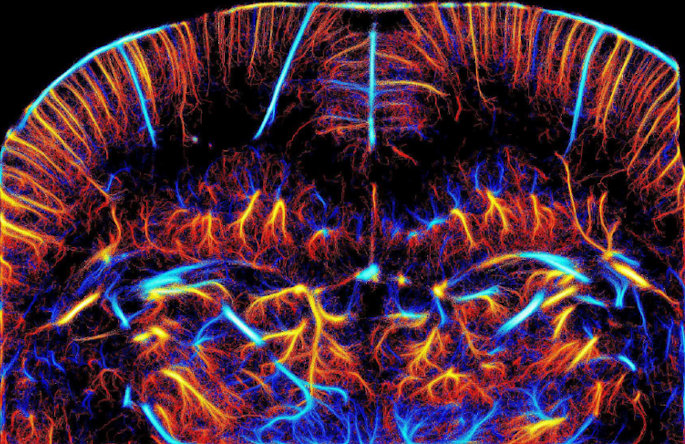

- ultrasound super-resolution imaging at the micron scale of capillary vessels in human organs, which constitute unique biomarkers of cancer growth, vascular pathologies or neurologic disorders